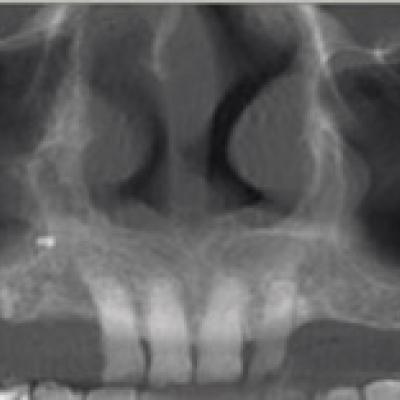

• Les différents clichés : possibilités et limites, avantages et inconvénients

• Diagnostic : du quotidien à l’exceptionnel